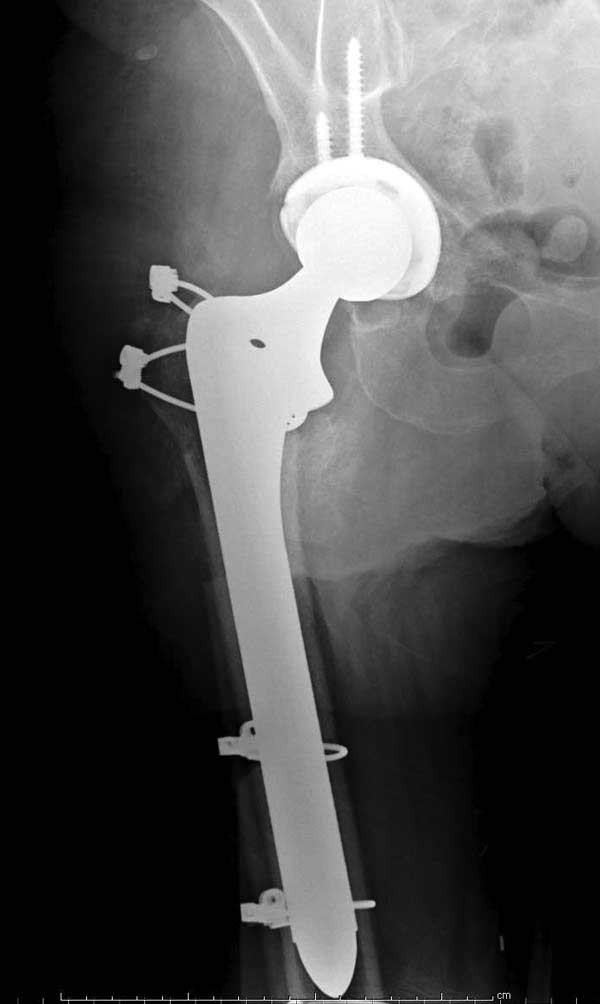

Такие “чужие осложнения” встречаются у всех и представляю банальный случай, который шаг за шагом показано как перерос в более сложный процесс... Больная 70 лет, множественные ко-морбидности, чрезвертельный перелом первоначально фиксирован Гамма 3. Осложнение в течение 6 недель, ревизия тотальной артропластикой и во время установки ножки обнаружена трещина диафиза (17), из малого доступа фиксация алло-графтом.

Обычно после чрезвертельных переломов, за исключением молодых, у пожилых остается нестабильность при движении. Часто падают и после 3х мес. в результате падения обнаружен перипротезный перелом (22-23), который зафиксирован Синтез пластиной.